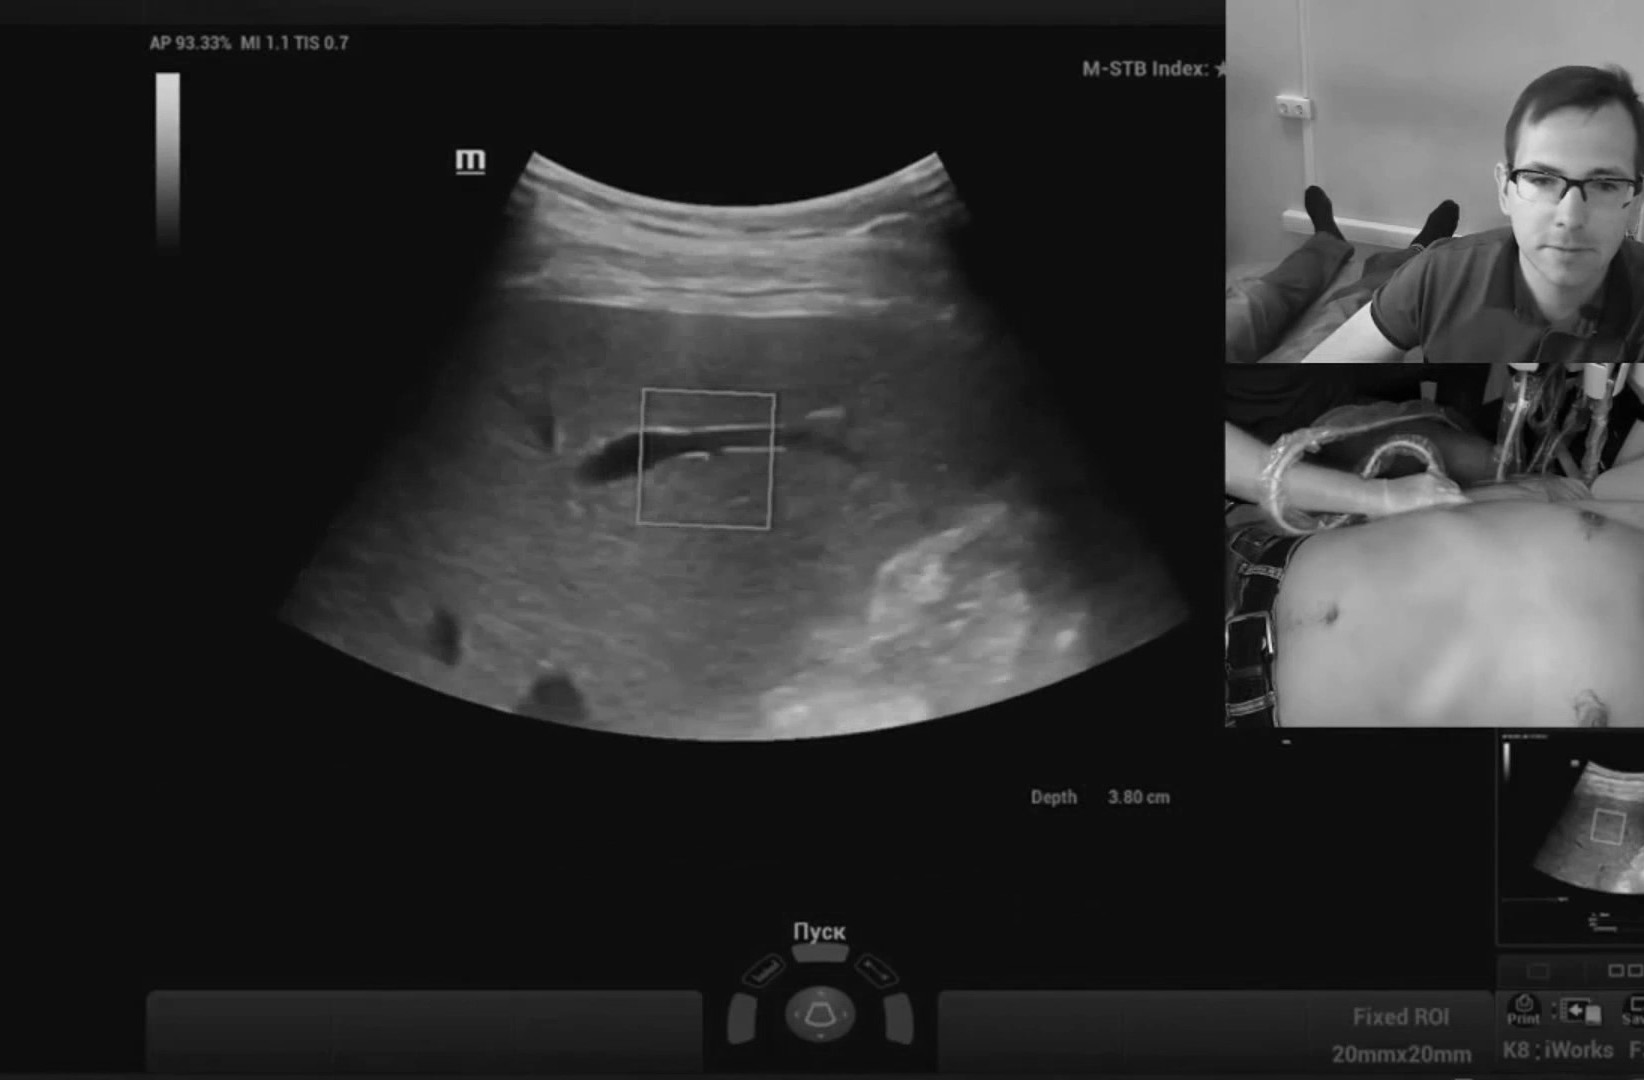

Работа с видео петлями реализована в полном объеме, то есть можно снять видео без оптимизации и отпустить пациента, оптимизацию провести уже на отснятых петлях в удобное время. Наличие эластографии сдвиговой волны периодически заставляет забыть, что я врач УЗД, бывают дни, когда делаешь одну эластографию печени. Очень популярная методика.